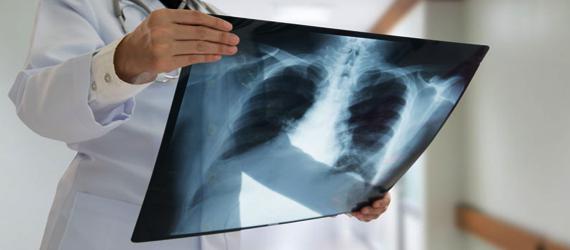

Radiografía

La radiografía de Rayos X detecta con facilidad fracturas de huesos, algunos tipos de tumores así como otras masas anormales, algunos tipos de lesiones, calcificaciones, la neumonía, etc. Es muy útil para mostrar algunos tejidos y órganos blandos.